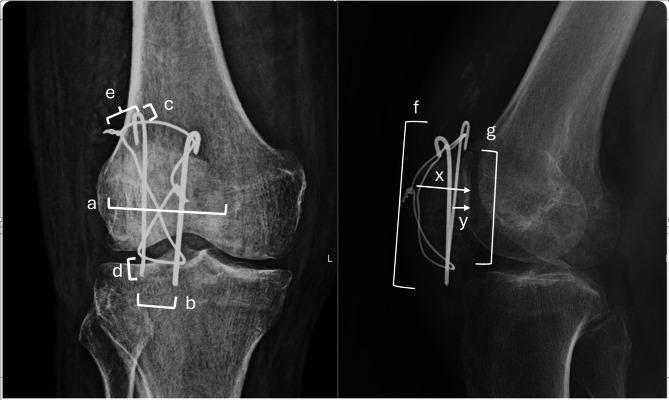

A total of 76 patients underwent surgical treatment for patellar fractures at Trakya University between January 2013 and December 2022. We retrospectively analyzed 32 patients who met the study's inclusion criteria for transverse fractures (AO Type 34- C1) treated with TBW. Radiographic parameters assessed included patellar width, inter-K-wire distance, K-wire-to-patella ratios, knot configuration, and K-wire length, all evaluated for their potential association with fixation failure. Failure was defined as cerclage wire slippage or breakage. Statistical analyses were conducted using SPSS and Jamovi software. Descriptive statistics, t-tests, chi-square or Fisher's exact tests, logistic regression, and ROC analysis were performed. A p-value < 0.05 was considered significant.

The mean age was 50 years ± 15.8 (range 26-80), with 8 women (25%) and 24 men (75%). Nine patients (28.1%) experienced TBW failure. Notably, single-knot constructs had significantly higher failure rates (66.7% vs. 19.2%; OR = 0.119, 95% CI [0.017-0.843], p = 0.038). Increased K-wire length was associated with failure (p = 0.008; cutoff 69.1 mm, AUC = 0.785). Patella-K-wire length ratio was higher in failures (p = 0.035). Lateral K-wire to articular distance and lateral K-wire to articular distance surface to patella thickness ratio were also significant predictors in slippage group (p = 0.046 and p = 0.031).